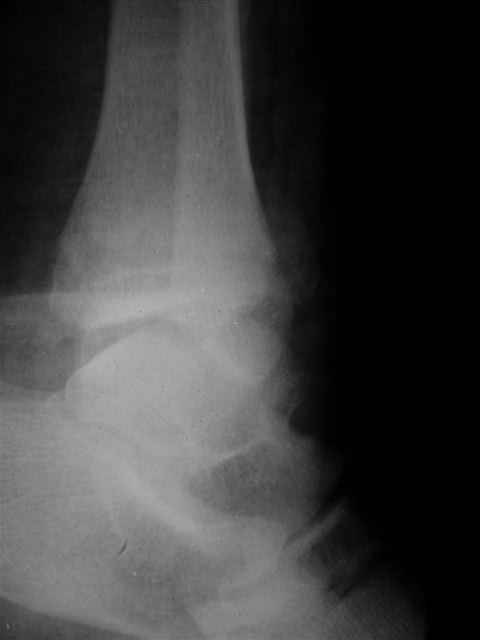

В первом письме я упомянул о закрытом повреждении правого голеностопного сустава, эверсионно-пронационный механизм травмы - перелом внутренней лодыжки( поперечный, на уровне суставной щели) и отрывной перелом бугорка Chaput. После обработки открытых переломов бедра и большеберцовой кости в эту же сессию перелом внутренней лодыжки фиксировал двумя расходящимися спицами, бугорок Chaput двумя тягловыми винтами 3,5 мм. Раны заживают благополучно. Учитывая повреждение наружной группы мышц, активное разгибание в голеностопном суставе ограничено. Пассивная + пассивно-активная мобилизация голеностопного сустава с физиотерапевтом.